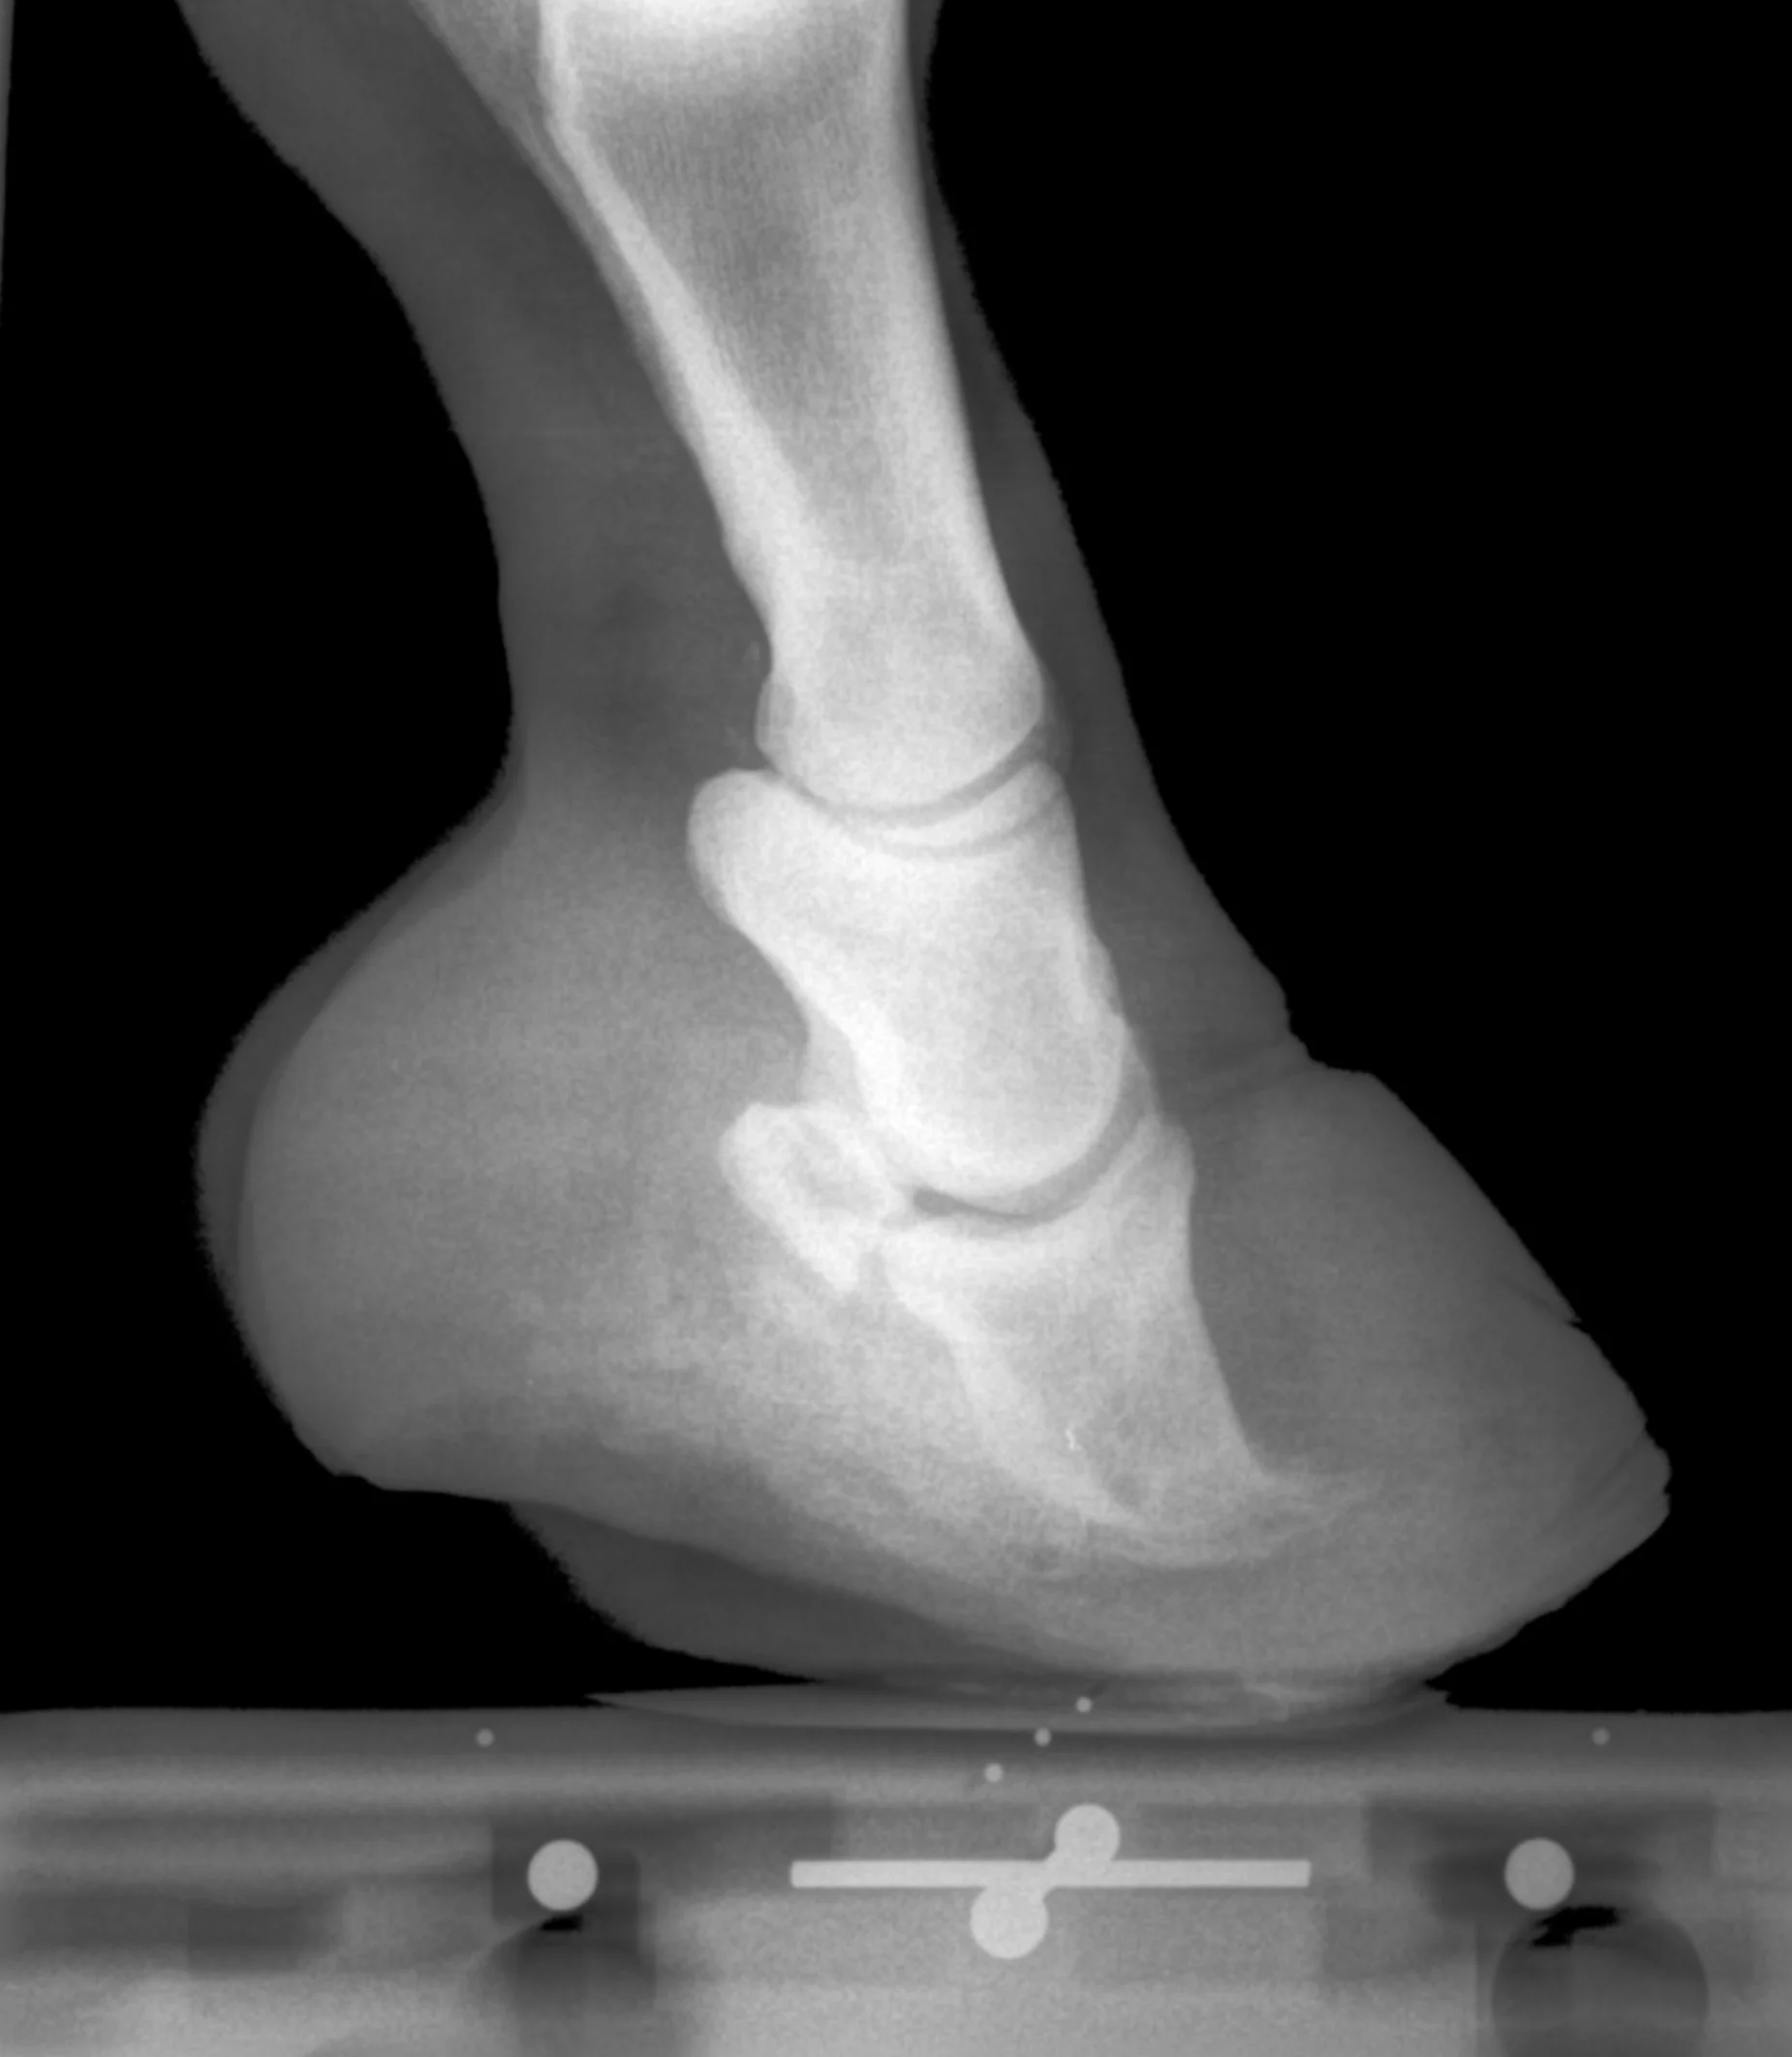

Pete - Chronic Founder View fullsize View fullsize View fullsize View fullsize View fullsize View fullsize View fullsize View fullsize View fullsize View fullsize